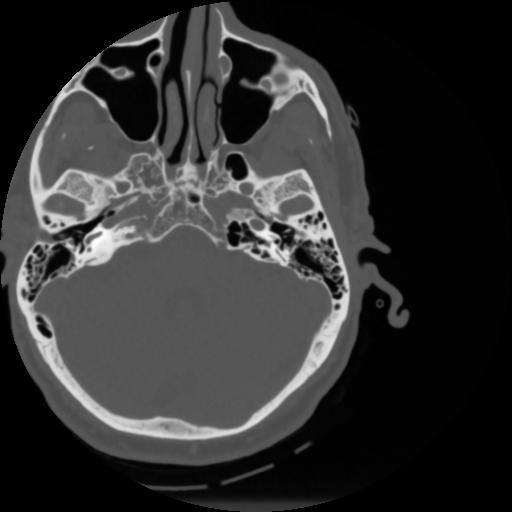

4 CEREBRO,,Vol,0.5,CEREBRO,,